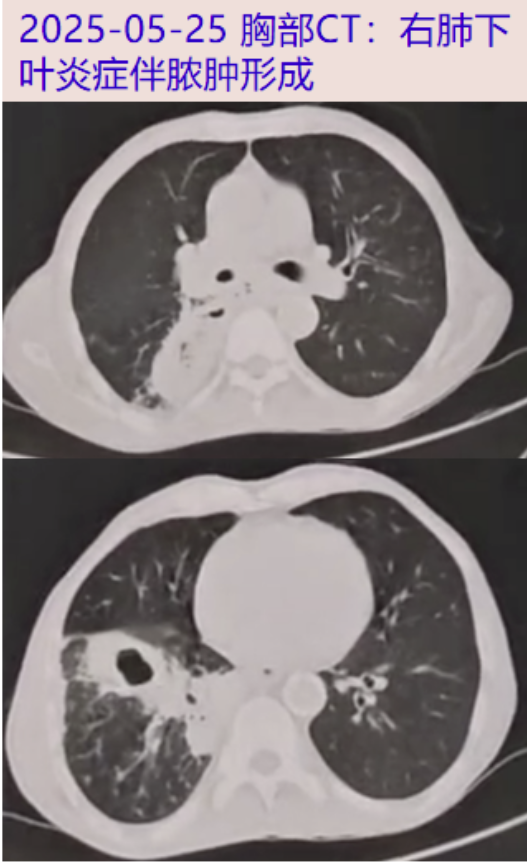

2025-05-25 出现咯血,为暗红色,共约5ml左右。当地医院查血常规:WBC 17.63×10^9/L,N 79.8%,Hb 105g/L;胸部CT: 右肺下叶炎症伴脓肿形成;予以抗感染(具体药物、剂量不详)、止咳、化痰等对症治疗。

胸腹盆增强CT: 右下肺脓肿,食管瘘机会大,食管中下段管壁增厚,右肺炎症,纵隔多发稍大淋巴结;右侧少量胸腔积液。前列腺增生伴钙化。盆腔少量积液。

2025-07-07 查血气(鼻导管3L/min吸氧):PH 7.52,PaCO2 39mmHg,PaO2 69mmHg(氧合指数 209)。血常规:WBC 19.50×10^9/L,N 83.5%,Hb 98g/L,Plt 452×10^9/L。炎症标志物:hsCRP 54.7mg/L,ESR 102mm/h,PCT 0.19ng/mL。生化:ALB 26g/L,余肝肾功能无殊。胸部增强CT:右肺多发炎症,右下肺脓肿形成, 食管瘘伴周围脓肿形成可能,右侧胸腔积液少量积液,较2025-06-05明显进展。